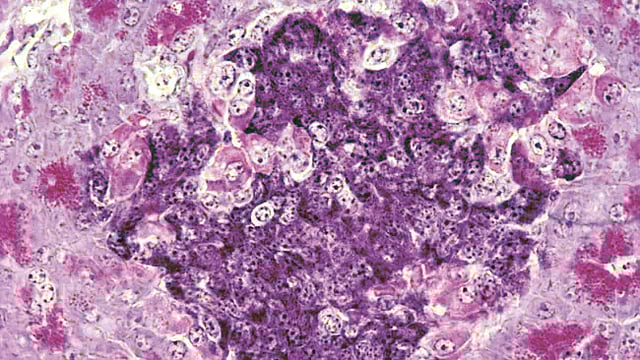

‘टाईप 1’ मधुमेहामध्ये शरीराची रोगप्रतिकारकशक्ती चुकून इन्सुलिन तयार करणार्‍या पेशींवरच हल्ला करते आणि त्या नष्ट करते. आतापर्यंत यावर उपाय म्हणून दात्याकडून मिळणार्‍या पेशींचे प्रत्यारोपण केले जात असे. मात्र, शरीर या नवीन पेशी स्वीकारण्यासाठी रुग्णाला आयुष्यभर अत्यंत कडक ‘इम्युनोसप्रेसंट’ औषधे घ्यावी लागत. या औषधांच्या दुष्परिणामांमुळे अशा प्रत्यारोपणाचा वापर मर्यादित होता. नुकत्याच झालेल्या एका संशोधनात संशोधकांनी ‘कायमेरिक’ किंवा ‘मिश्र’ रोगप्रतिकार यंत्रणा विकसित केली आहे.

यामध्ये रुग्ण आणि दाता या दोघांच्याही रोगप्रतिकार यंत्रणेचे घटक एकत्र करण्यात आले. यामुळे उंदरांच्या शरीराने कोणत्याही दीर्घकालीन औषधांशिवाय इन्सुलिन तयार करणार्‍या नवीन पेशींचा स्वीकार केला. वॉशिंग्टन युनिव्हर्सिटीतील तज्ज्ञ डॉ. जॉन डिपेर्सिओ यांच्या मते, ‘हा मधुमेहावर कायमस्वरूपी उपचार करण्याचा एक संभाव्य मार्ग आहे. सैद्धांतिकद़ृष्ट्या हे एक खूप मोठे पाऊल आहे.’ संशोधकांनी एकाच दात्याकडून मिळणार्‍या ‘अस्थिमज्जा स्टेम सेल्स’ आणि ‘आयलेट सेल्स’ यांचा वापर केला. या प्रक्रियेत स्टेम सेल्स शरीरात गेल्यावर पांढर्‍या पेशींची पुन्हा निर्मिती करतात.